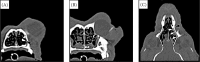

Figure 3. CT-dacryocystography with a bone window setting (window width 2 000 HU, window level 600 HU)

At the level of the nasolacrimal duct opening (A) and nasolacrimal canal (B), the patency of the lacrimal drainage is confirmed by detection of the contrast medium in the nasal meatus (arrowhead). The reconstructed dorsal plane (C) shows the intact left nasolacrimal duct and canal (arrows). The cystic lesion located in the left maxilla is not related to the nasolacrimal duct